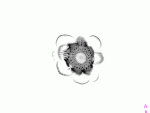

Guess what this is?

Yep, an artichoke :)